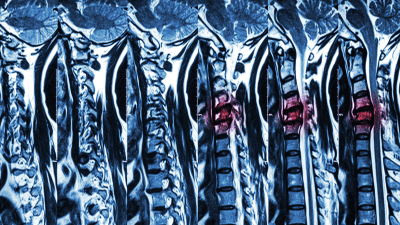

Magnetic resonance imaging (MRI) is a powerful diagnostic tool used to evaluate spine pathology.